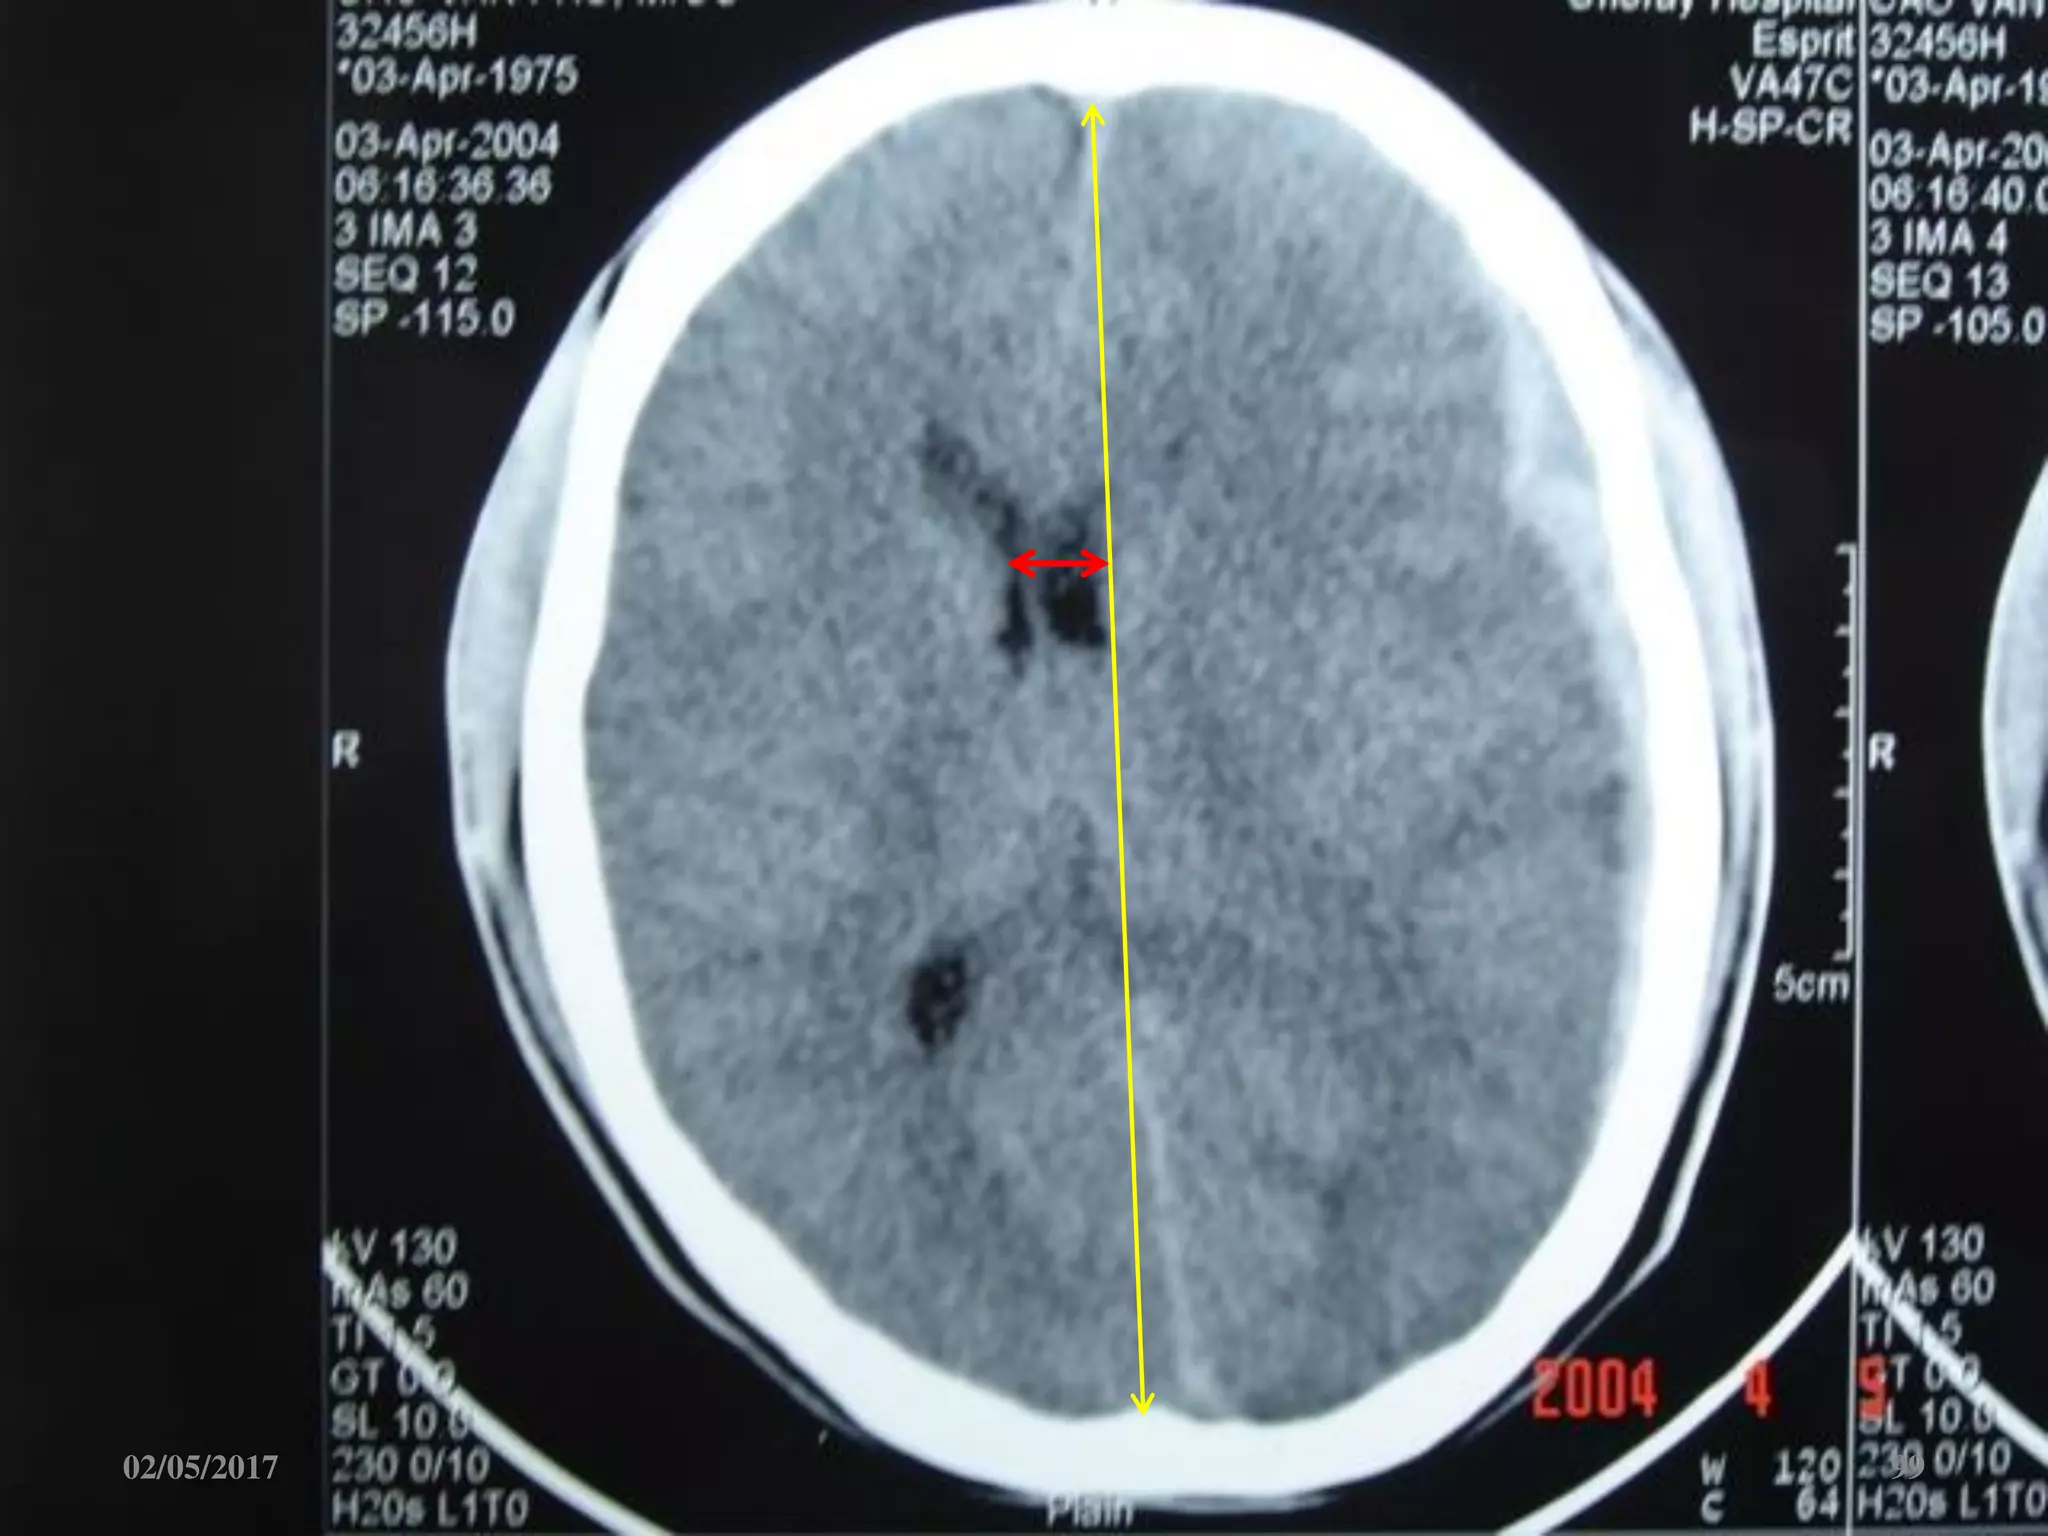

Phù não

• Giảm đậm độ lan tỏa.

• Mất ranh giới chất

trắng-xám.

• Xóa các rãnh não-bể

não.

• Não thất 2 bên nhỏ.

Phù não • Giảmđậm độ lan tỏa. • Mất ranh giới chất trắng-xám. • Xóa các rãnh não-bể não. • Não thất 2 bên nhỏ. 02/05/2017 67